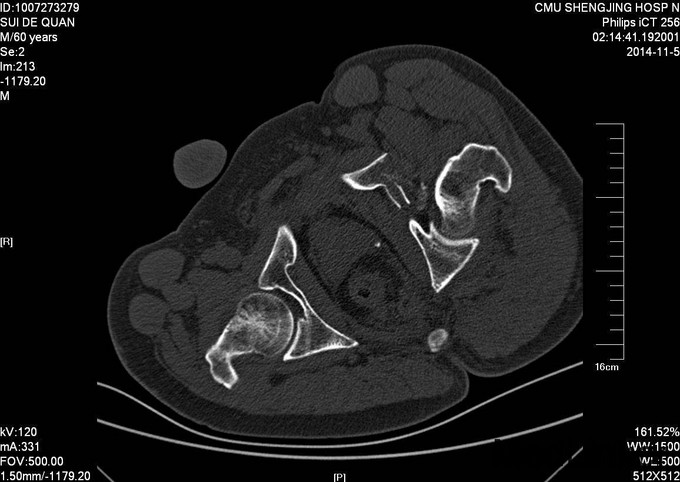

1.患者老年男性,以“车祸左髋部疼痛活动受限3天”为主诉入院。 2.现病史:患者自述于2014-11-04日晚下午7点发生机动车肇事,伤后患者急救车送往孤山二院,诊断为左髋臼骨折,当地医院未经任何治疗。急来中国医科大学附属盛京医院第五骨科创伤骨科治疗。我科以“左髋臼骨折”为主要诊断收入院。今来我院就诊,患者病来一般状态可,生命体征平稳,无发烧无发热,饮食睡眠可。

专科查体:患者平车入病房,左腿内收内旋屈曲畸形,左髋部压痛(+),叩击痛(+),骨盆分离试验阳性,活动受限,双下肢感觉未见异常,活动可,双侧足背动脉搏动可触及,双侧足趾活动灵活。

入院后急诊行左髋关节脱位复位术,左胫骨结节骨骼牵引术。术后牵引7公斤,完善相关检查后,全麻下行左髋臼骨折切开复位内固定术。术后患者生命体征平稳,卧床。术后14天拆线后出院,回当地医院继续治疗。